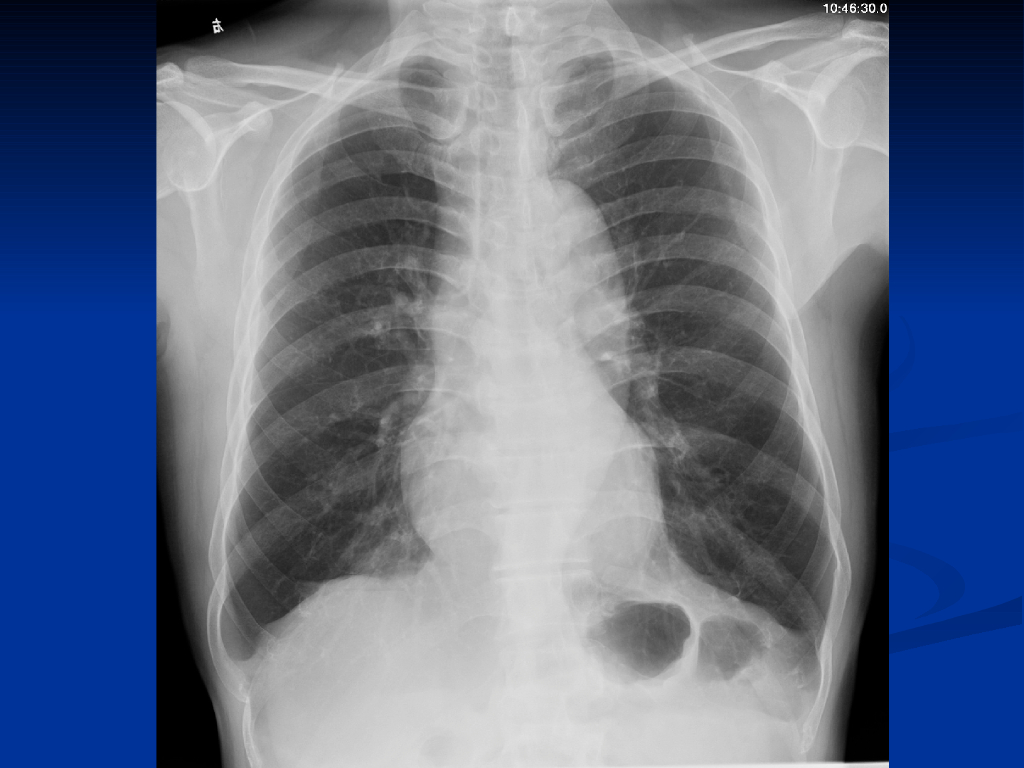

《放射诊断学》循环系统异常影像学表现.pdf